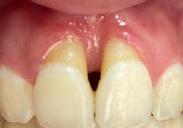

Lâexamen exobuccal Ă©tait sans particularitĂ©s. Lâexamen endobuccal a objectivĂ© une inflammation marginale modĂ©rĂ©e Ă sĂ©vĂšre gĂ©nĂ©ralisĂ©e avec un indice dâOleary Ă 68%, un indice gingival (BoP = Bleeding on Probing) Ă 76%, et un trama occlusal sur 42 (Figure 1). Le bilan parodontal montre des sites avec une profondeur de sondage (PS) de 12mm, et plus de 50% des dents prĂ©sentant une perte dâattache â„ 5mm. Le bilan radiographique a montrĂ© des pertes osseuses terminales, avec un rapport perte osseuse/Ăąge Ă 4,5 (Figure 1)

La thĂ©rapeutique Ă©tiologique a consistĂ© en une Ă©ducation Ă lâhygiĂšne bucco-dentaire, une Ă©limination des facteurs de rĂ©tention de plaque, lâextraction 42+rĂ©section radiculaire et rĂ©alisation dâune contention en fibre de verre avec la couronne ; dâune instrumentation non chirurgicale supra et sous gingivale

par quadrant (3) combinĂ©e Ă une antibiothĂ©rapie (3,4). Une chirurgie avec lambeau dâaccĂšs selon la technique du lambeau avec incision intrasulculaire (open flap) a Ă©tĂ© rĂ©alisĂ©e sur la 46. Une thĂ©rapie parodontale de soutien associĂ©e Ă une phase correctrice a Ă©tĂ© mise en place aprĂšs la thĂ©rapie parodontale active (5). La rĂ©habilitation orale a consistĂ© dans un premier temps Ă rĂ©aliser une correction orthodontique (Figure 2) ; et dans un second temps la conception dâune Ă©pithĂšse gingivale (Figure 3)

AprĂšs 6 mois, pas de profondeurs de poches â„ 6mm, avec un indice de plaque Ă 9% et un indice gingival < 10%. La thĂ©rapeutique non chirurgicale a permis un gain dâattache

stable qui sâest traduit par une diminution des profondeurs de sondage en regard de la 11, 21, et 36 dont le pronostic Ă©tait dĂ©favorable, mais aussi lâapparition dâimportantes rĂ©cessions postthĂ©rapeutique (Figure 4). La chirurgie avec lambeau dâaccĂšs a permis Ă©galement dâamĂ©liorer le niveau osseux de la 46. Le pronostic gĂ©nĂ©ral Ă long terme de la patiente a Ă©tĂ© amĂ©liorĂ©.

La réévaluation Ă 3 mois a montrĂ© une amĂ©lioration de lâĂ©tat parodontal avec plus de 90% de sites prĂ©sentant des PS †4mm (3). LâefficacitĂ© du dĂ©bridement mĂ©canique non chirurgical associĂ© Ă un bon contrĂŽle de plaque individuel dans le traitement des parodontites sĂ©vĂšres a Ă©tĂ© largement documentĂ©e dans plusieurs revues systĂ©matiques (6). Toutefois, la prĂ©sence dâune poche rĂ©siduelle de 6mm avec saignement au sondage sur la 46 reprĂ©sentait un rĂ©sultat incomplet et a nĂ©cessitĂ© dans notre cas un traitement chirurgical par lambeau dâaccĂšs afin dâĂ©viter la progression de la maladie (7).

La rĂ©cession post-thĂ©rapeutique est une observation commune aprĂšs une instrumentation non chirurgicale, particuliĂšrement au niveau des poches profondes et/ou dâun phĂ©notype gingival fin. Notre patiente prĂ©sentait une RT3 sur les incisives centrales rendant son sourire inesthĂ©tique (trou noir). Les restaurations dentaires directes et indirectes et/ou Ă©pithĂšses pouvant ĂȘtre envisagĂ©es (5) ; nous avons optĂ© pour une solution moins invasive en rĂ©alisant une Ă©pithĂšse gingivale. Peu coĂ»teuse et pratique, elle a permis dâoptimiser le rĂ©sultat esthĂ©tique et fonctionnel dans un contexte socio-Ă©conomique limitĂ©.

Figure 4 : (a) Vue clinique Ă 6 mois ; (b) bilan radiographique Ă 3mois (b) ; (c) Retro alvĂ©olaire sur la 46 avant et aprĂšs lambeau dâassainissement